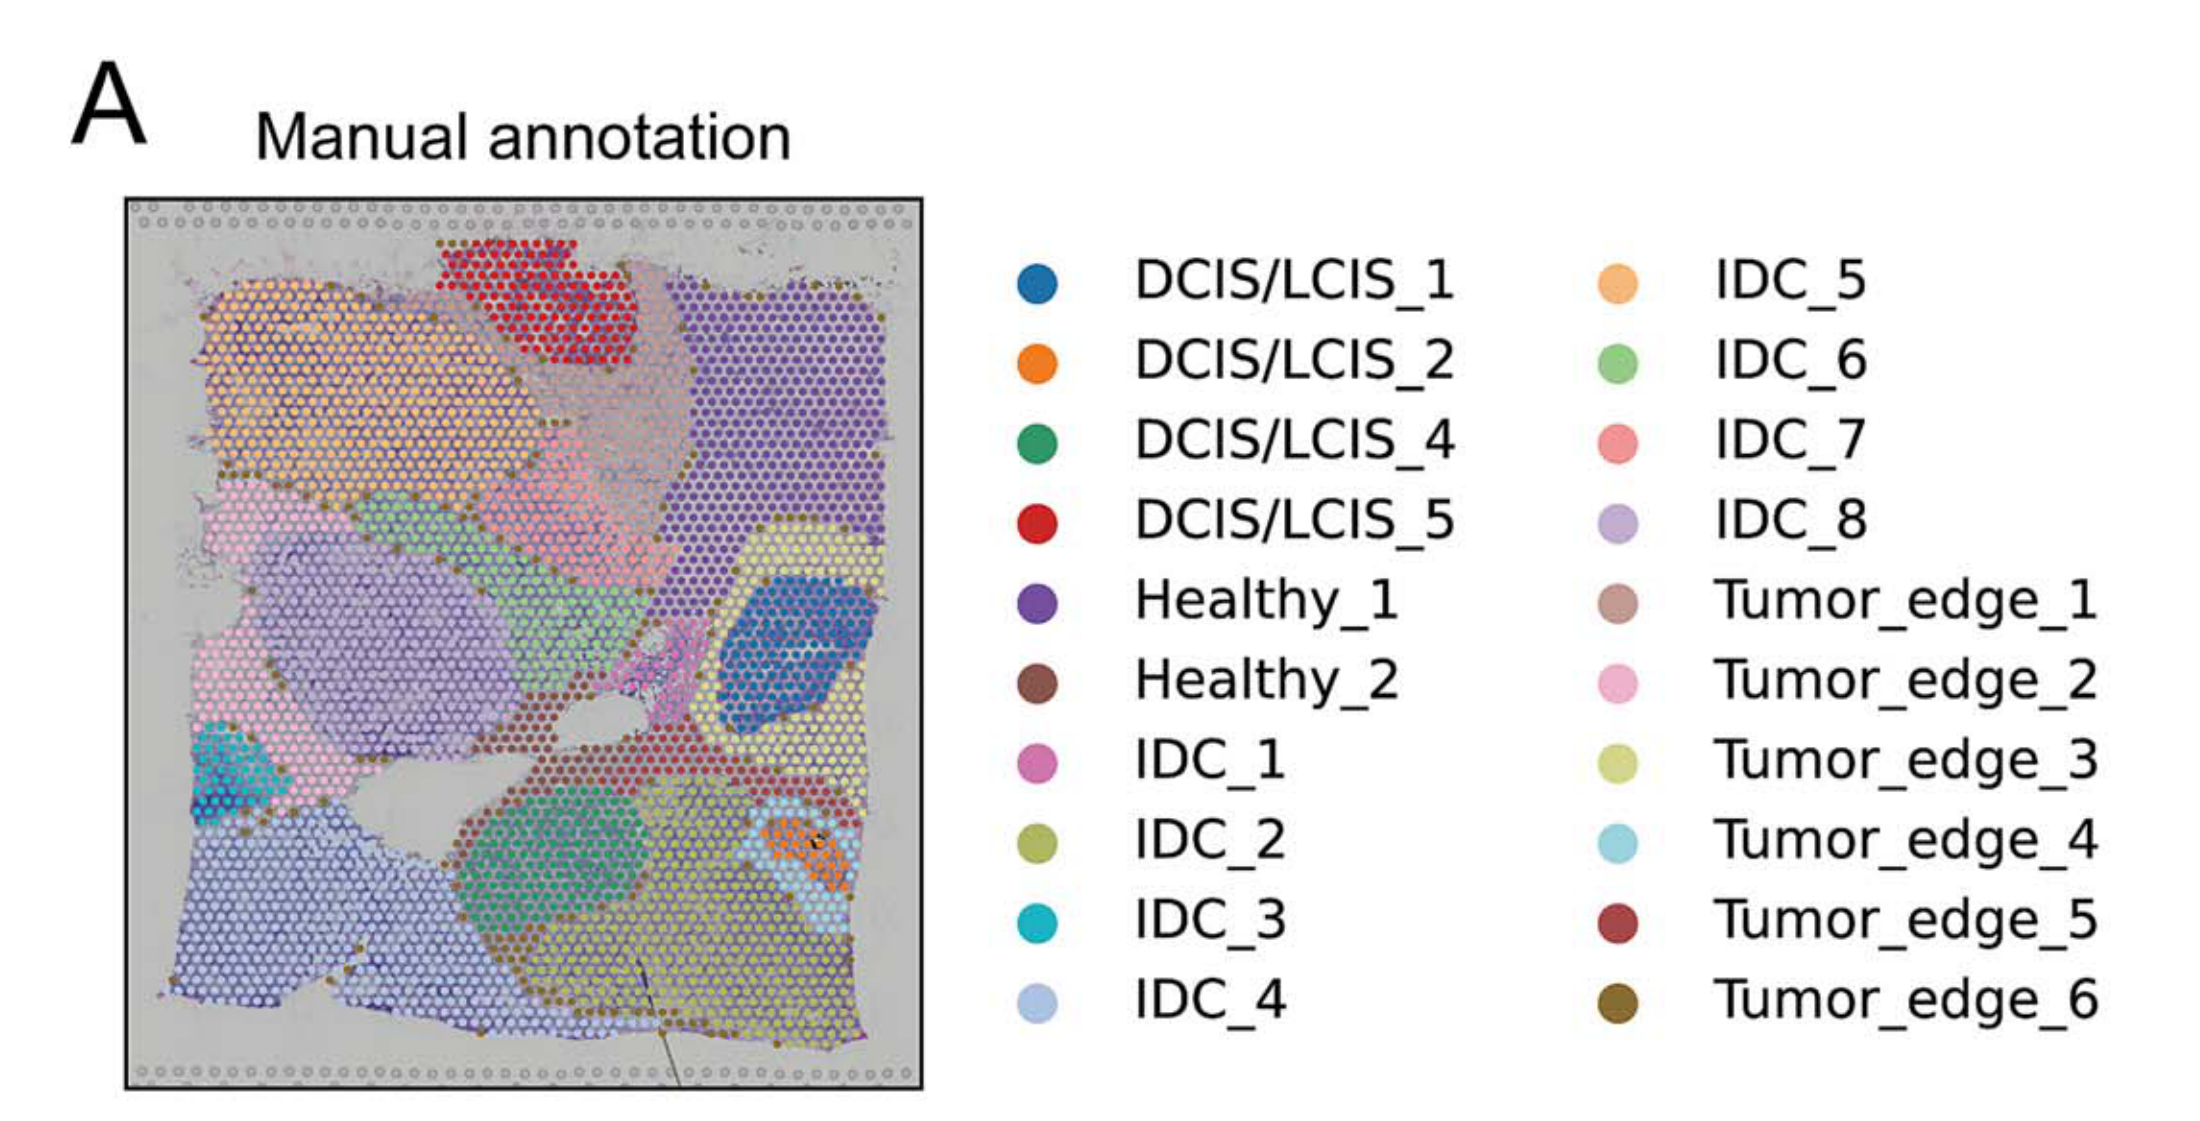

What is the spatial distribution of disease subtypes?

What is the tissue morphology and architecture?